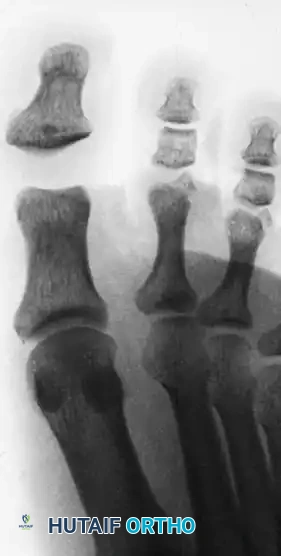

* Radiographic Appearance: The hallmark is marked widening of the interphalangeal joint space without gross dorsal displacement.

Anteroposterior radiograph demonstrating a Miki Type I dislocation with marked widening of the interphalangeal joint space due to an incarcerated plantar plate.

Lateral view of the same Miki Type I injury. Note the wide joint space; the distal phalanx is not grossly hyperextended, which can mask the severity of the incarceration.